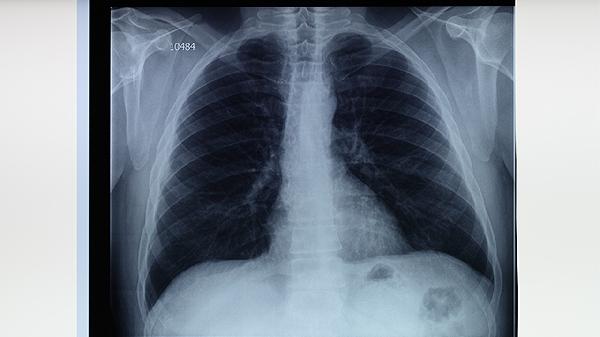

空洞型肺结核是由结核杆菌引起的慢性传染病。当病人肺内形成空洞时,结核杆菌数量会大幅增加,通过咳嗽、打喷嚏、说话时形成的飞沫扩散至空气中。健康人吸入这些悬浮的飞沫颗粒后,结核杆菌可在肺部感染繁殖。如果免疫力较弱,感染风险更高。